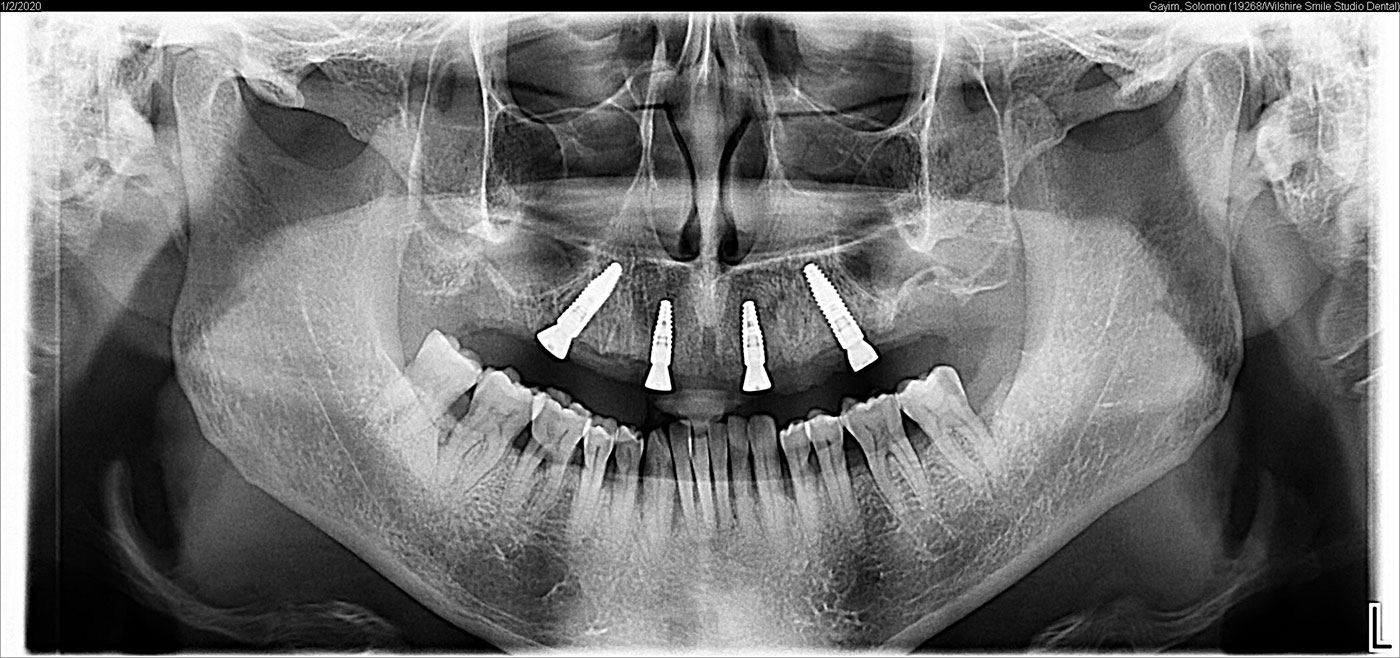

Unfortunately, removable partial dentures do not stop this process, but in fact, accelerate it. Any kind of denture is only a temporary solution and it is extremely uncomfortable and hinders normal speech and taste. Dentures often cause significant change in facial form and can be cosmetically displeasing. An alternative to a complete or partial denture for appropriately selected patients is the All-on-4 Dental Implant. This is anchored in the bone with strategically-placed implants, allowing your restorative dentist to replace 10 to 12 teeth for each of the four dental arches. This process is somewhat different than other forms of full mouth dental rehabilitation, enabling a much faster process to replace lost teeth, while avoiding the necessity of extensive bone augmentation surgery, which would take a long time to heal. This gives your dentist cost-effective, predictable, and excellent results.